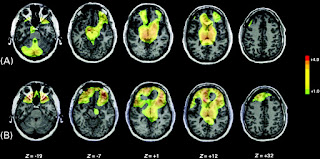

I then looked into more scientific ways of interpreting sleep and its effect, exploring the different lines and patterns created through different types of brain scans and checks. This could be a very interesting route to go down in terms of representing the effects sleep can have on the body; it is an instant and universal representation of health and well being.